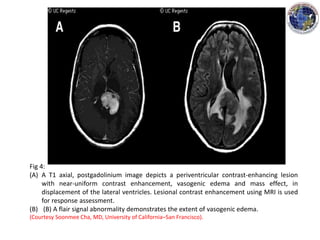

Fig 4:

(A) A T1 axial, postgadolinium image depicts a periventricular contrast-enhancing lesion

with near-uniform contrast enhancement, vasogenic edema and mass effect, in

displacement of the lateral ventricles. Lesional contrast enhancement using MRI is used

for response assessment.

(B) (B) A flair signal abnormality demonstrates the extent of vasogenic edema.

(Courtesy Soonmee Cha, MD, University of California–San Francisco).